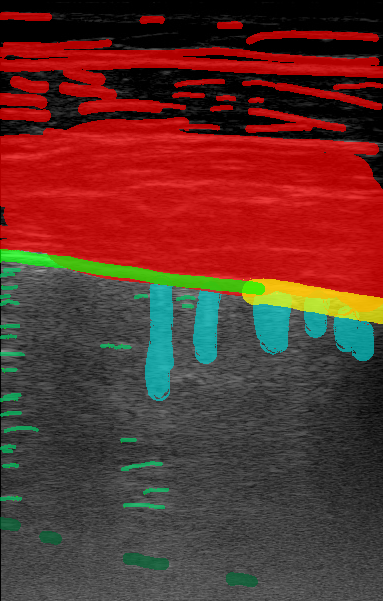

Figure 1 is an example segmentation label, thresholded by confidence to show the distribution of confidences in a single example. As the confidence threshold increases, the resulting segmentation labels get more refined. However, there may be a loss of features in the labels once the thresholds get sufficiently higher than the expert’s confidence in that feature’s appearance. For example, vertical lines disappear once the threshold becomes 40% in Figure 1. By thresholding the confidence labels this way and conducting further analysis with downstream tasks, we can gain a sense of how prominent these LUS features need to be for them to be clinically relevant.

The performance of our models in segmenting specific lung ultrasound features is represented in Figure 3. None of the models demonstrated a consistent advantage across all features, highlighting that each model possessed relative strengths and weaknesses depending on the visual characteristics of the target. For example, the model trained with 100% confidence labels performed best at segmenting features that typically appear as intensely bright, relatively isolated large areas, such as certain vertical artifacts (B-lines) and sub-A lines. These features may be easier to delineate due to their high contrast and limited overlap with surrounding structures. In contrast, models trained with lower thresholds, such as the 50% confidence model, performed relatively well on pleural features, indicating that this model is potentially better at identifying structures that are less uniformly bright or more linear and contiguous, such as the pleural line itself, which requires recognizing a specific pattern along a boundary. Across the models, there was a general tendency to struggle with thin, elongated structures like a sharp pleural line and fine sub-A lines, while performing better on features that occupy larger areas of the image or have a more amorphous appearance, such as a thickened, "fuzzy" pleura or fascia bands in the chest wall.

Figure 4 shows example segmentation outputs for the same test example shown in Figure 1. Each image represents the segmentation output of a model trained with the relevant confidence threshold. Similar to the expert labels, the segmented clinical features tend to get more refined as the confidence threshold increases. The 100% model tends to over-segment features, while the 100% model misses some features entirely, as expected.